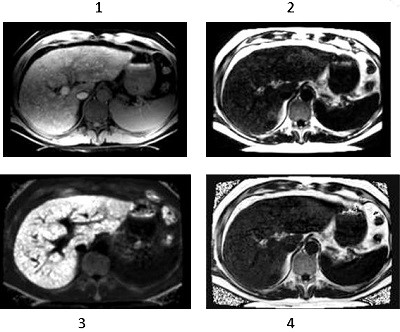

IDEAL IQ is a software option intended for use on GE MR systems. IDEAL IQ is capable of producing transverse, sagittal, coronal, and oblique images of internal structures of the body, including but not limited to, the musculoskeletal, breast, abdominal, and neurological systems. Specific anatomical regions that may be imaged include the abdomen, breast, spine, joints, and extremities. IDEAL IQ is an acquisition and reconstruction technique that simultaneously obtains independent images of hydrogen nuclei that resonate at different frequencies to provide separation of water and triglyceride fat.

IDEAL IQ generates images of separated water and triglyceride fat, relative triglyceride fat fraction map, and tissue transverse magnetization relaxation. In the liver, the relative triglyceride fat fraction map is quantitative; it reflects the proton density (number of protons per unit volume) of triglyceride fat, divided by the sum of the proton density of triglyceride fat and the proton density of water, on a voxel-by-voxel basis.

The combination of the R2* map with the triglyceride fat-signal fraction map enables IDEAL IQ to improve the accuracy of tissue characterization parameters (R2* or triglyceride fat) by removing contamination from multiple chemical components.